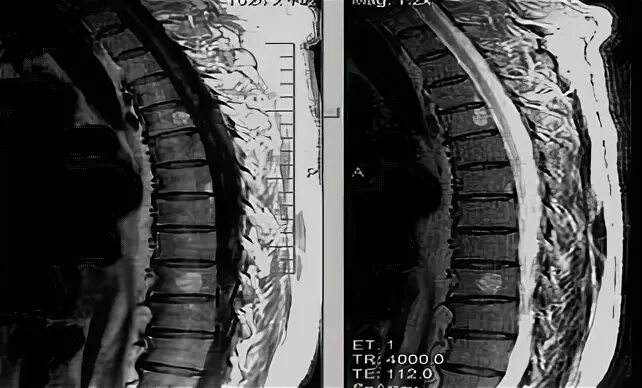

Метастазы в грудном отделе